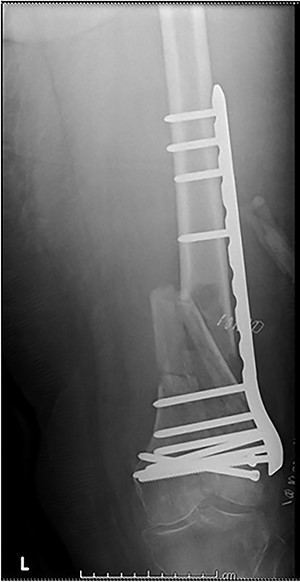

Case 2 (Figs 3–5): here difficulties were clearly encountered in achieving satisfactory reduction in the coronal plane. The screw immediately proximal to the fracture line is too close to the fracture.

Selecting a longer plate would have allowed proximal screws to sit more appropriately in order to reduce the risk of plate fatigue.